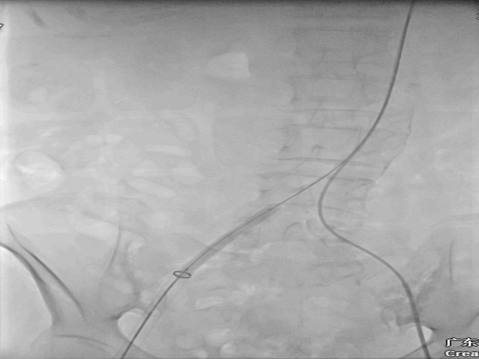

20F大鞘中DSA发现右股夹层DSA

8*60外周球囊扩张DSA